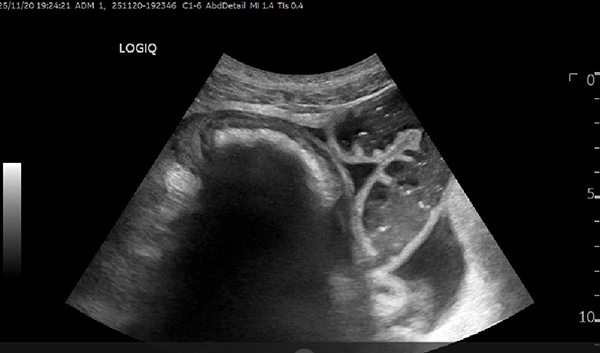

超声诊疗科主任医师刘翠红带领进修医师张修丽、相林以及规培医师、研究生等,通过胃肠超声实时动态监测,实时观察结石位置、形态变化及肠壁状况,协同调整导管位置,评估治疗效果,为治疗提供了精准的影像学依据。

经结肠梗阻导管造影术

结石变成松散两小块